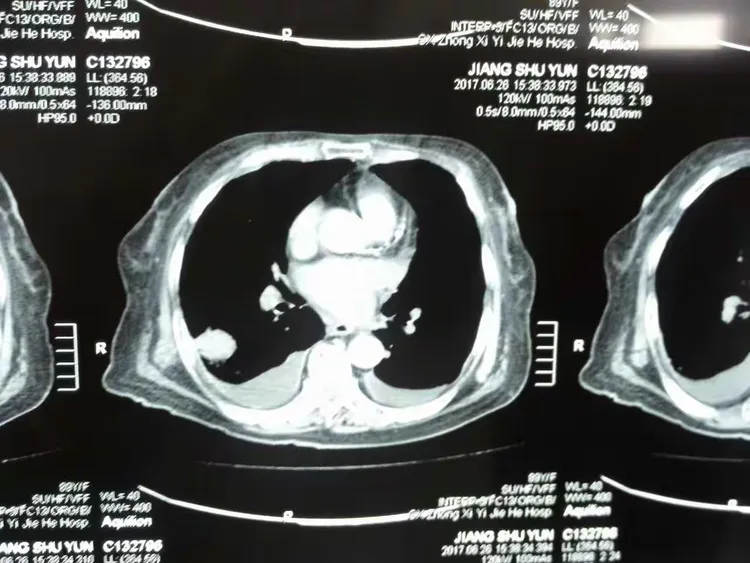

这个月的复查结果糟透了,肺上肿瘤疯长,已经发生了一次咳血。现在没有[s0]射波刀后肿瘤会消失吗[s1]是不是做了肺部穿刺就一定是肺肿瘤或者肺癌?[s2]图片[s3]肺上长肿瘤严重吗 小红书[s4]肺上良性肿瘤怎么办才能消除[s5]确诊为肺癌晚期。医生告知王阿姨,肿瘤发展较快,手术治疗的机会不大。[s6]后,医生的诊断结果让所有人震惊——是肺部恶性肿瘤,且已经是晚期了。[s7]右肺尖肿瘤,16个月迅速长大[s8]吸烟30年,虽已戒烟5年,但这个患者的肺黑得吓人,肺上的恶性肿瘤更加触目惊心![s9]岳母肺部肿瘤病情演变[s10]肺部肿瘤[s11]新方法可能减少肺部肿瘤的生长[s12]微信图片_20190404112215.jpg[s13]胸部肿瘤综合治疗之一肺癌篇~~~科大二附院胸外科胡举副主任医师治疗体会[s14]考虑肺部肿瘤[s15]肺部的恶性肿瘤[s16]肺部肿瘤[s17]右肺上叶肿瘤,穿刺难度大,患者高龄基础疾病多,手术中并发症风险大。[s18]麻烦给看一下我的肺部有肿瘤吗?谢谢了?[s19]肺上肿瘤切除手术好做吗(肺部肿瘤位置尴尬)(1)[s20]肺部巨大肿瘤[s21]少见!6厘米巨大肺部肿瘤—兖矿新里程总医微创切除![s22]查发现患者肺部也有一个肿瘤,考虑患者原发肿瘤在肺部,脑部是转移瘤。[s23]右肺上叶贴水平裂的肿瘤,手术切除范围的考量(病例回顾)[s24]肺部长肿瘤的症状[s25]这是一名35岁女性,左肺上叶将近4厘米的肿物,没有任何症状,查体时才发现,4厘米的肿瘤都没有临床症状,还是很可怕的。腔镜下切除,淋巴结应该不至于有转移,还是略偏早期,但术后是需要靶向药物治疗或者化疗的,尽量降低复发概率。所以,肿瘤不能等有了症状再就诊,分期晚了医生也没有办法。[s26]以前照片[s27]患者高龄基础疾病多,手术中并发症风险大。术前ct见右上肺肿瘤术中操作[s28]肺肿瘤影像大汇总,看完深刻理解[s29]发展,甚至肺上的肿瘤已经缩小了百分之四十,于是在2019年1月3日出院了。在进行了四个疗程的治疗后,[s30]肺上长肿瘤严重吗 mip.haodf.com[s31]肺上长肿瘤严重吗 来自网易[s32]右肺尖肿瘤,16个月迅速长大[s33]肺肿瘤有哪些危害[s34]肺肿瘤[s35]肿瘤标记物虽然是正常的,但是咳嗽原因不明,ct却发现肺上长了肿物.[s36]肺部恶性肿瘤需要手术吗能治好吗[s37]肺上长了肿瘤必须要做穿刺检查吗?[s38]肺部肿瘤能治好吗[s39]